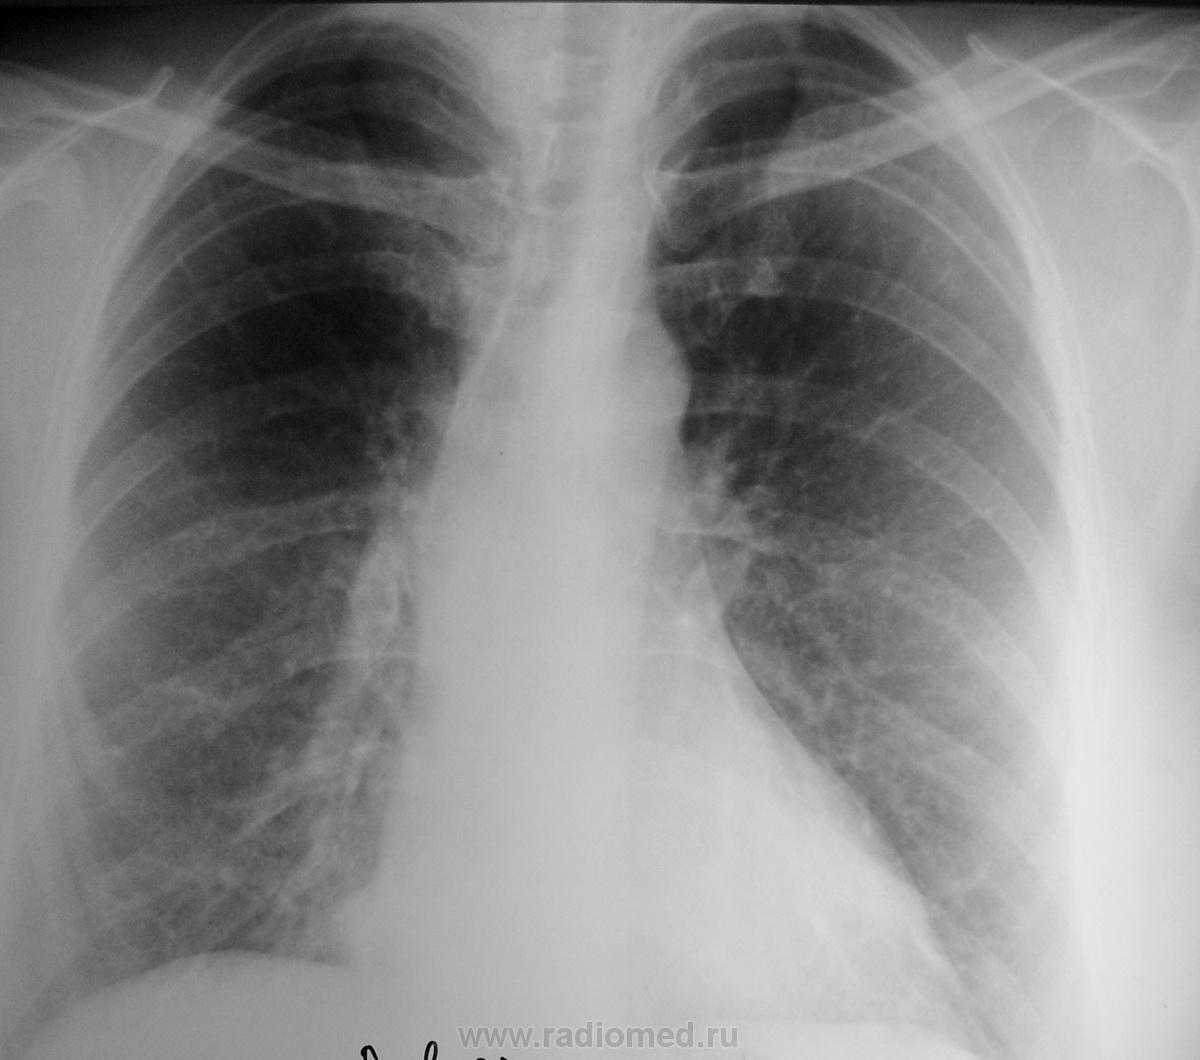

Пол пациента: Женский пол Тип патологии: Инфекция Область исследования: Грудная клетка и верхние дыхательные пути Методы исследования: Rg Женщина 50 лет обратилась с жалобами к терапевту по поводу высокой температуры(39) и кашля, была направлена на снимок. Я поставил пневмонию в S5 правого лёгкого, но немного засомневался. Что скажут уважаемые коллеги? https://radiomed.ru/sites/default/files/styles/case_slider_image/public/user/712/sl274012.jpg?itok=m1MWVr3r ID:17022 Чт, 24/11/2011 - 20:43 #1 DR.RAD Не на сайте Был на сайте: 11 лет 9 месяцев назад Зарегистрирован: 25.03.2009 - 18:22 Публикации: 805 да инфильтрация сомнительна Чт, 24/11/2011 - 22:43 #2 Bob Не на сайте Был на сайте: 11 лет 11 месяцев назад Зарегистрирован: 20.08.2011 - 20:06 Публикации: 218 есть только в S7 Чт, 24/11/2011 - 21:44 #3 Nikolas Не на сайте Был на сайте: 2 месяцев 1 неделя назад Зарегистрирован: 21.12.2010 - 20:37 Публикации: 4559 с носоглоткой у пациентки, точно, не все в порядке. Чт, 24/11/2011 - 22:36 #4 И.Бондаренко Не на сайте Был на сайте: 2 дня 5 часов назад Зарегистрирован: 13.09.2011 - 22:55 Публикации: 9206 Посмотрим, что покажет лечение. Возможно, вы и правы. Чт, 24/11/2011 - 22:45 #5 stovbav Не на сайте Был на сайте: 2 года 2 месяцев назад Зарегистрирован: 20.12.2009 - 17:28 Публикации: 7066 Все таки есть небольшое локальное утолщение передне-базального отдела косой м\долевой плевры справа, да и рядом смазаность легочного рисунка, так что истина недалеко. А вот контроль не помешает. Болезни ног: виды, симптомы, причины, профилактика и лечение Пт, 25/11/2011 - 02:09 #6 Makcimalist Не на сайте Был на сайте: 11 лет 9 месяцев назад Зарегистрирован: 08.05.2010 - 14:28 Публикации: 1994 stovbav wrote: Все таки есть небольшое локальное утолщение передне-базального отдела косой м\долевой плевры справа, да и рядом смазаность легочного рисунка, так что истина недалеко. А вот контроль не помешает. - При таком застое в МКК отмеченные Вами изменения бывают. Инфильтрации в паренхиме не усматриваю... пока! -------------- "Просто, по видимости, не видеть логики в очевидных вещах - это тоже одно из свойств некоторых умов, наряду с грустными думами о свойствах ума других." © Vega 08/10/2011

да инфильтрация сомнительна

есть только в S7

Все таки есть небольшое локальное утолщение передне-базального отдела косой

м\долевой плевры справа, да и рядом смазаность легочного рисунка, так что истина недалеко. А вот контроль не помешает.

- При таком застое в МКК отмеченные Вами изменения бывают.

Инфильтрации в паренхиме не усматриваю... пока!